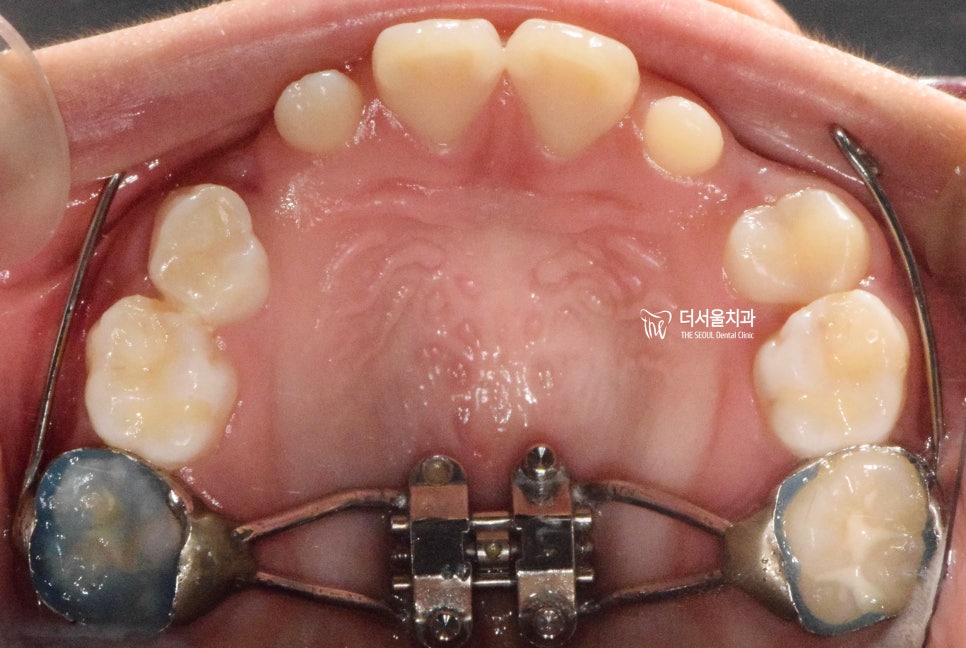

『구강 내 사진』

성장교정 이 필요한 이유는,

구강 내 사진에서도 뚜렷히 찾아볼 수 있습니다.

유치가 빠지면서 영구치아가 올라오고 있는

혼합치열기에서, 영구치가 올라올 수 있는

충분한 공간을 확보하면서

턱의 위치를 바로 잡는것이 핵심포인트입니다.

우선 여기서 봐야 될 큰 문제는

1) 절단교합(Edge to edge bite) 입니다.

윗니가 아랫니를 물고 있어야 되는데,

서로 절단연끼리 맞닿고 있죠.

그러면서, 성장교정 을 통해서

위턱의 크기를 발달시키며

아래턱은 억제시켜야 되는 상황입니다.